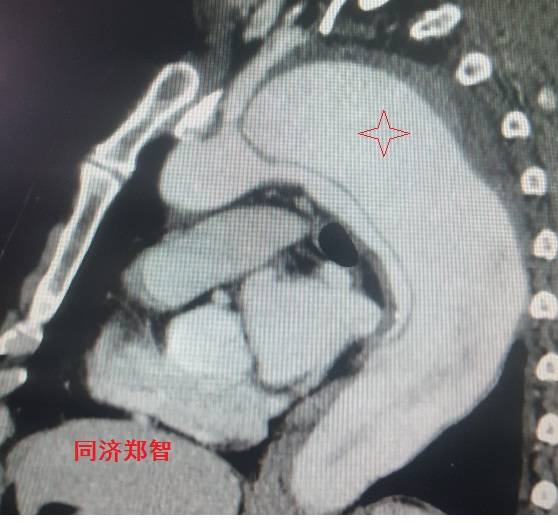

病例二

胸部平扫CT提示升主动脉增宽(红色星形标记),CTA证实A型主动脉夹层伴升主动脉夹层动脉瘤形成。